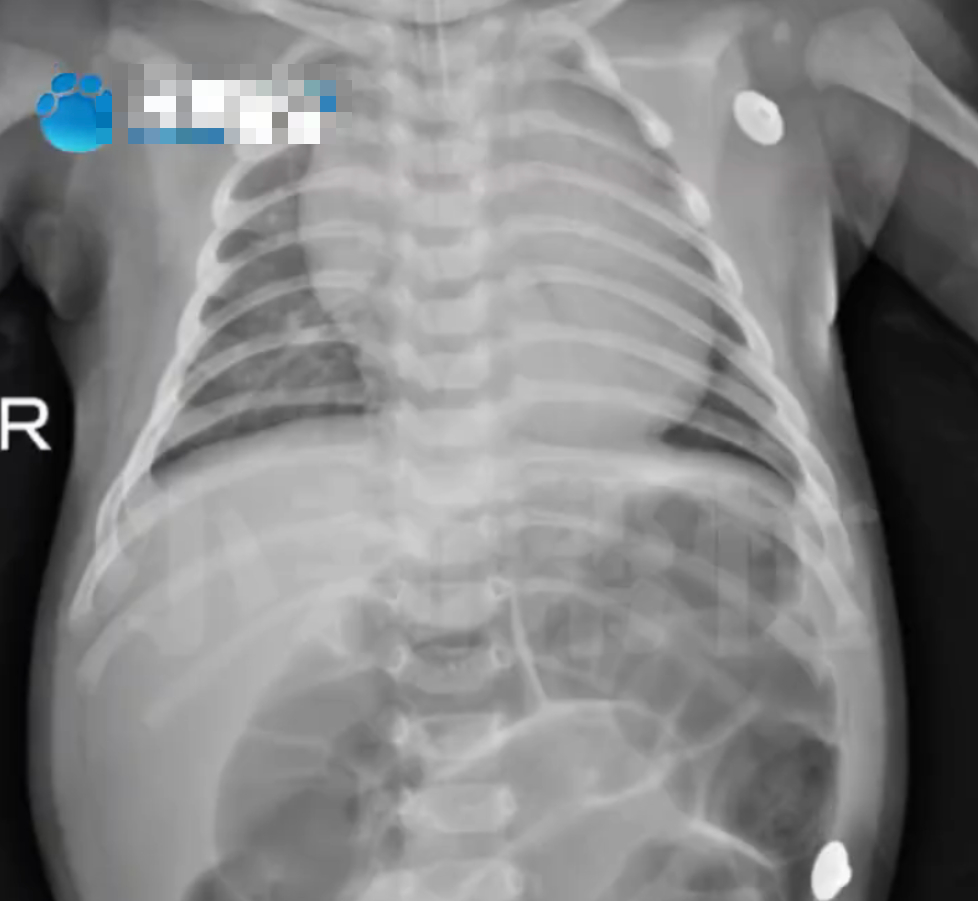

| Em bé 52 ngày tuổi nhập viện trong tình trạng bụng phình to, suy hô hấp vì ngộ độc Botulinum |

Một vụ việc thương tâm xảy ra tại Hà Nam (Trung Quốc) khiến nhiều người, nhất là các gia đình có con nhỏ phải giật mình. Cụ thể, một bé gái chỉ mới 52 ngày tuổi nhập viện cấp cứu tại Bệnh viện nhi đồng Hà Nam trong tình trạng bụng phình to, khó thở nghiêm trọng. Kết quả chẩn đoán là ngộ độc Botulinum nguy kịch.